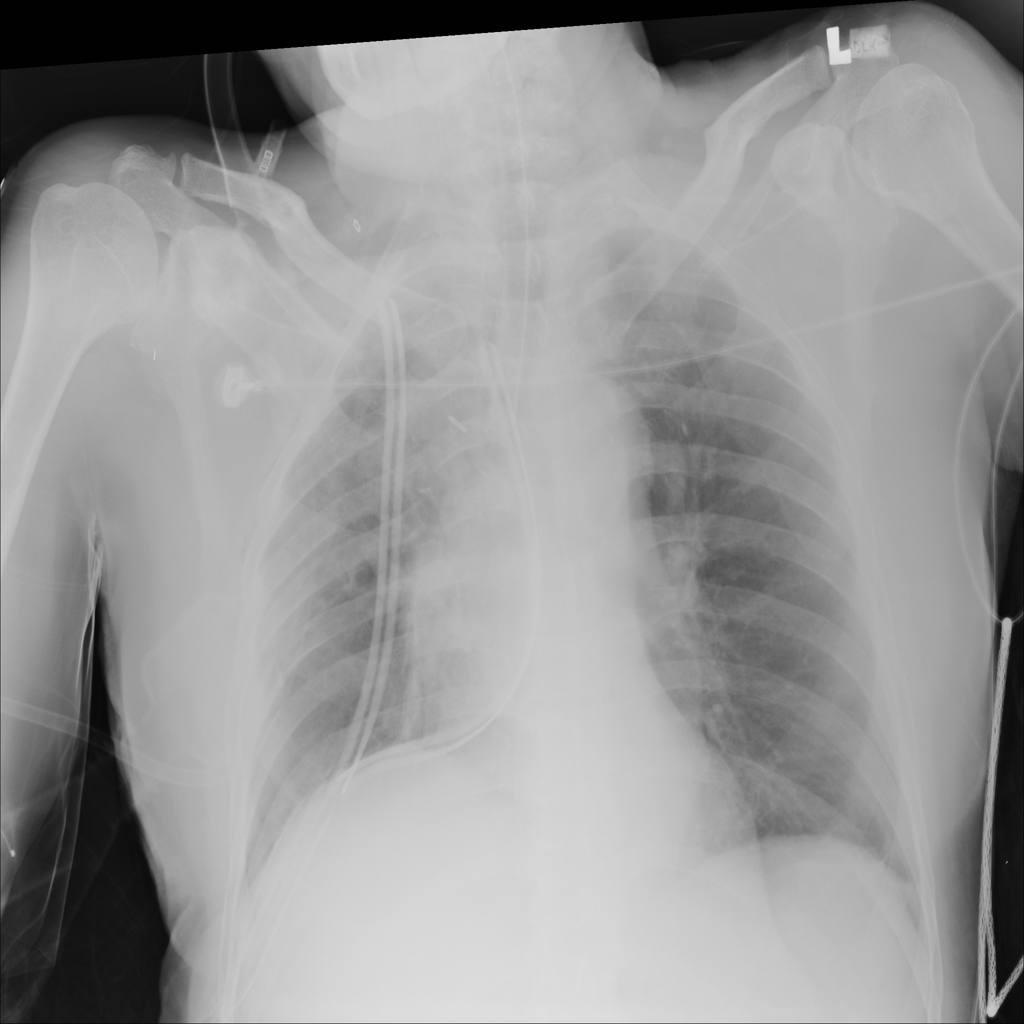

PAT-4639 · IMG-024Mass

PAT-4639 · IMG-024

AP